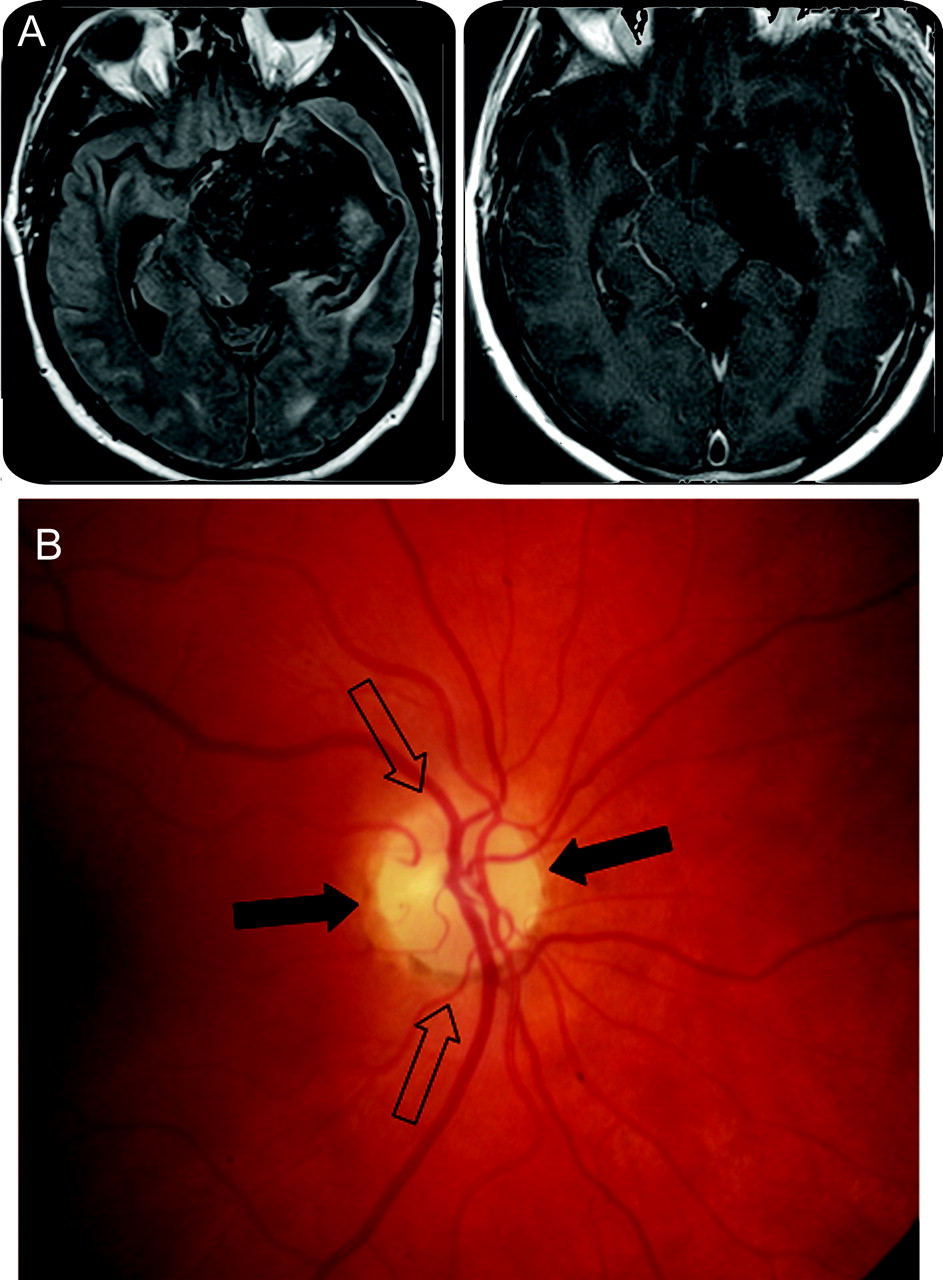

一名46岁男子。右视野赤字和几个月的记忆丧失。他经历了完整的表皮样瘤切除左侧桥小脑角这个演讲之前10年。考试,视力正常,明显有同向偏盲对抗视神经盘的苍白。大脑的核磁共振研究展示了一种大损伤扩展到中颅窝和涉及左视神经束(图)。他再次接受手术和术后MRI表现出明显的缺陷在该地区的左视神经束(图)。病理证实了周期性的表皮样瘤。

(一)术前和术后MRI。(B)领结萎缩。从视网膜鼻纤维视神经盘和纤维鼻窝但时间盘项目中央部分的视神经(黑色箭头)。纤维的视网膜颞形成两极视神经盘(空心箭头)。